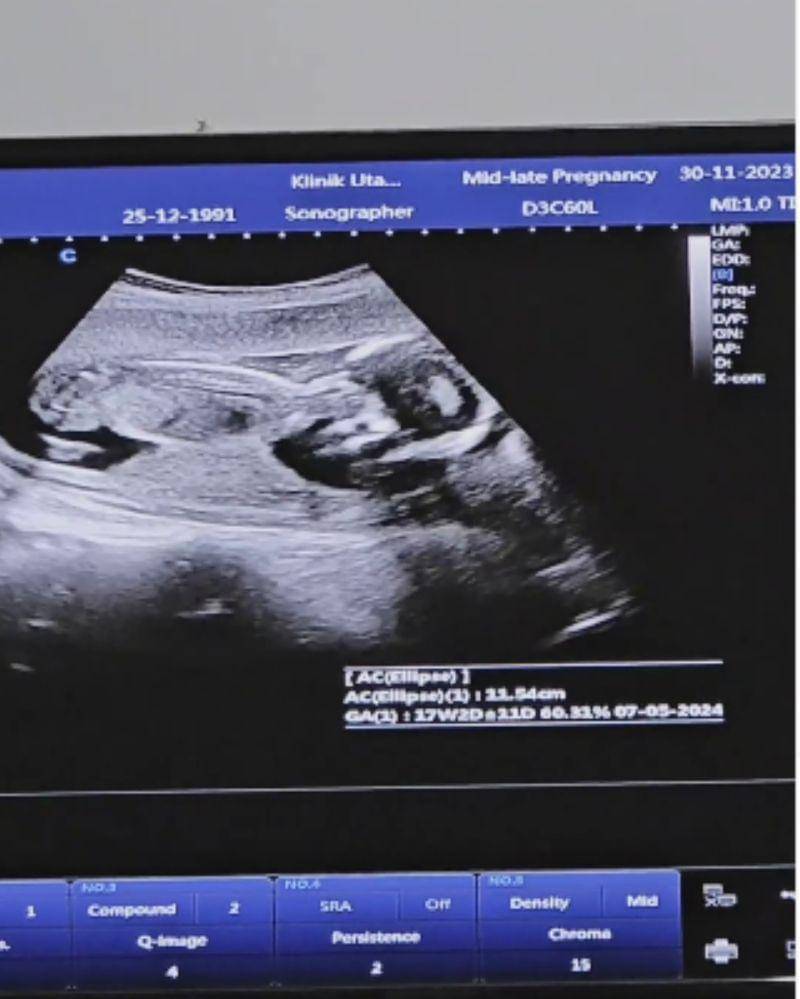

Alyssa juga terlihat memamerkan pemeriksaan kehamilannya. Terlihat usia kehamilan Alyssa sudah menginjak usia 17 minggu lebih satu hari. Rekaman pemeriksaan kehamilan Ica tersebut diambil pada tanggal 30 November 2023 yang lalu.